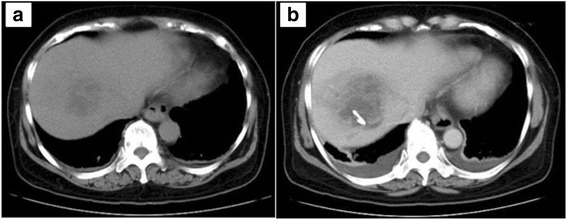

Fig. 1.

Computed tomography scans. Plain computed tomography showing a low-density lesion in the right lobe of the liver at admission to our hospital (a). Enhanced computed tomography showing an unresolved liver abscess on day 6, which was drained percutaneously (b)

A 64-year-old woman with an unremarkable medical history was admitted to a nearby hospital for a high fever and diarrhea that had lasted for 1 week. She had vision loss in her right eye, exacerbation of renal dysfunction (serum creatinine level, 4.96 mg/dL), and thrombocytopenia (platelet count, 14,000/μL) within 48 h from initial presentation. Therefore, she was transferred to our institution for treatment of severe infectious disease. On admission, she was alert and had no alteration of mental status, no hypoxia on room air, and normal vital signs (temperature, 36.7 °C; blood pressure, 126/80 mmHg; pulse rate, 74 beats/min; respiratory rate, 12 breaths/min). However, she had almost complete ablepsia of the right eye. Laboratory data showed severe inflammation (white cell count, 21,700/μL; C-reactive protein level, 28.2 mg/dL; procalcitonin, 46.4 ng/mL), liver dysfunction (aspartate transaminase, 147 IU/L; alanine transaminase, 345 IU/L), thrombocytopenia (platelet count, 32,000/μL), an increased serum creatinine level (1.35 mg/dL), and coagulopathy (fibrin/fibrinogen degradation product, 56.6 μg/mL; D-dimer, 24.2 μg/mL; prothrombin time-international normalized ratio, 1.15)(Table 1). Computed tomography showed a low density area in the right lobe of the liver, and she was diagnosed with a liver abscess (Fig. 1a). Broad-spectrum antibiotic therapy with meropenem (3 g/day) was immediately started. Endogenous endophthalmitis of the right eye was also diagnosed, and emergency vitrectomy was performed on the day of admission. The blood culture at admission showed K. pneumoniae, and the antibiotic therapy was changed to ceftriaxone (2 g/day) on day 4 because all of the cephalosporin had high susceptibility (Table 2) and ceftriaxone was known to penetrate to the liver in high concentration, which was continued to day 14. Percutaneous drainage of the liver abscess, which was unresolved by medical treatment, was performed after coagulopathy improved on day 6 (Fig. 1b). The culture of the drainage fluid also showed K. pneumoniae. The drainage tube was removed on day 14, and the patient was discharged in a good general condition on day 22, with an additional 2-week course of oral levofloxacin on days 14–28. However, she had complete ablepsia of the right eye. Capsular probing via PCR for the presence of magA (serotype K1) and K2A (serotype K2) genes was performed by using the magA-specific primers (forward, 5′-GGTGCTCTTTACATCATTGC-3′; and reverse, 5′-GCAATGGCCATTTGCGTTAG-3′) and k2A-specific primers (forward, 5′-CAACCATGGTGGTCGATTAG-3′; and reverse, 5′-TGGTAGCCATATCCCTTTGG-3′) as previously described[7]. The virulence-associated gene rmpA was also screened using PCR by using the rmpA-specific primers (forward, 5′- ACTGGGCTACCTCTGCTTCA-3′; and reverse, 5′- CTTGCATGAGCCATCTTTCA-3′) as previously described [8]. The reaction mixtures of these samples were kept at 95 °C for 5 min, followed by 35 cycles of 95 °C for 1 min, 50 °C for 1 min, and 72 °C for 1 min and then 72 °C for 7 min. The K2A gene, which is consistent with the K2 serotype, was detected by PCR. PCR was also positive for the virulence-associated gene rmpA. To assess for the presence of hypermucoviscosity, a string test was performed on the organism grown in 5 % sheep blood agar. The formation of a mucous string of >5 mm in length after touching a colony with a loop was considered positive [9]. The isolated K. pneumoniae had a positive string test consistent with a hypermucoviscous phenotype (Fig. 2).